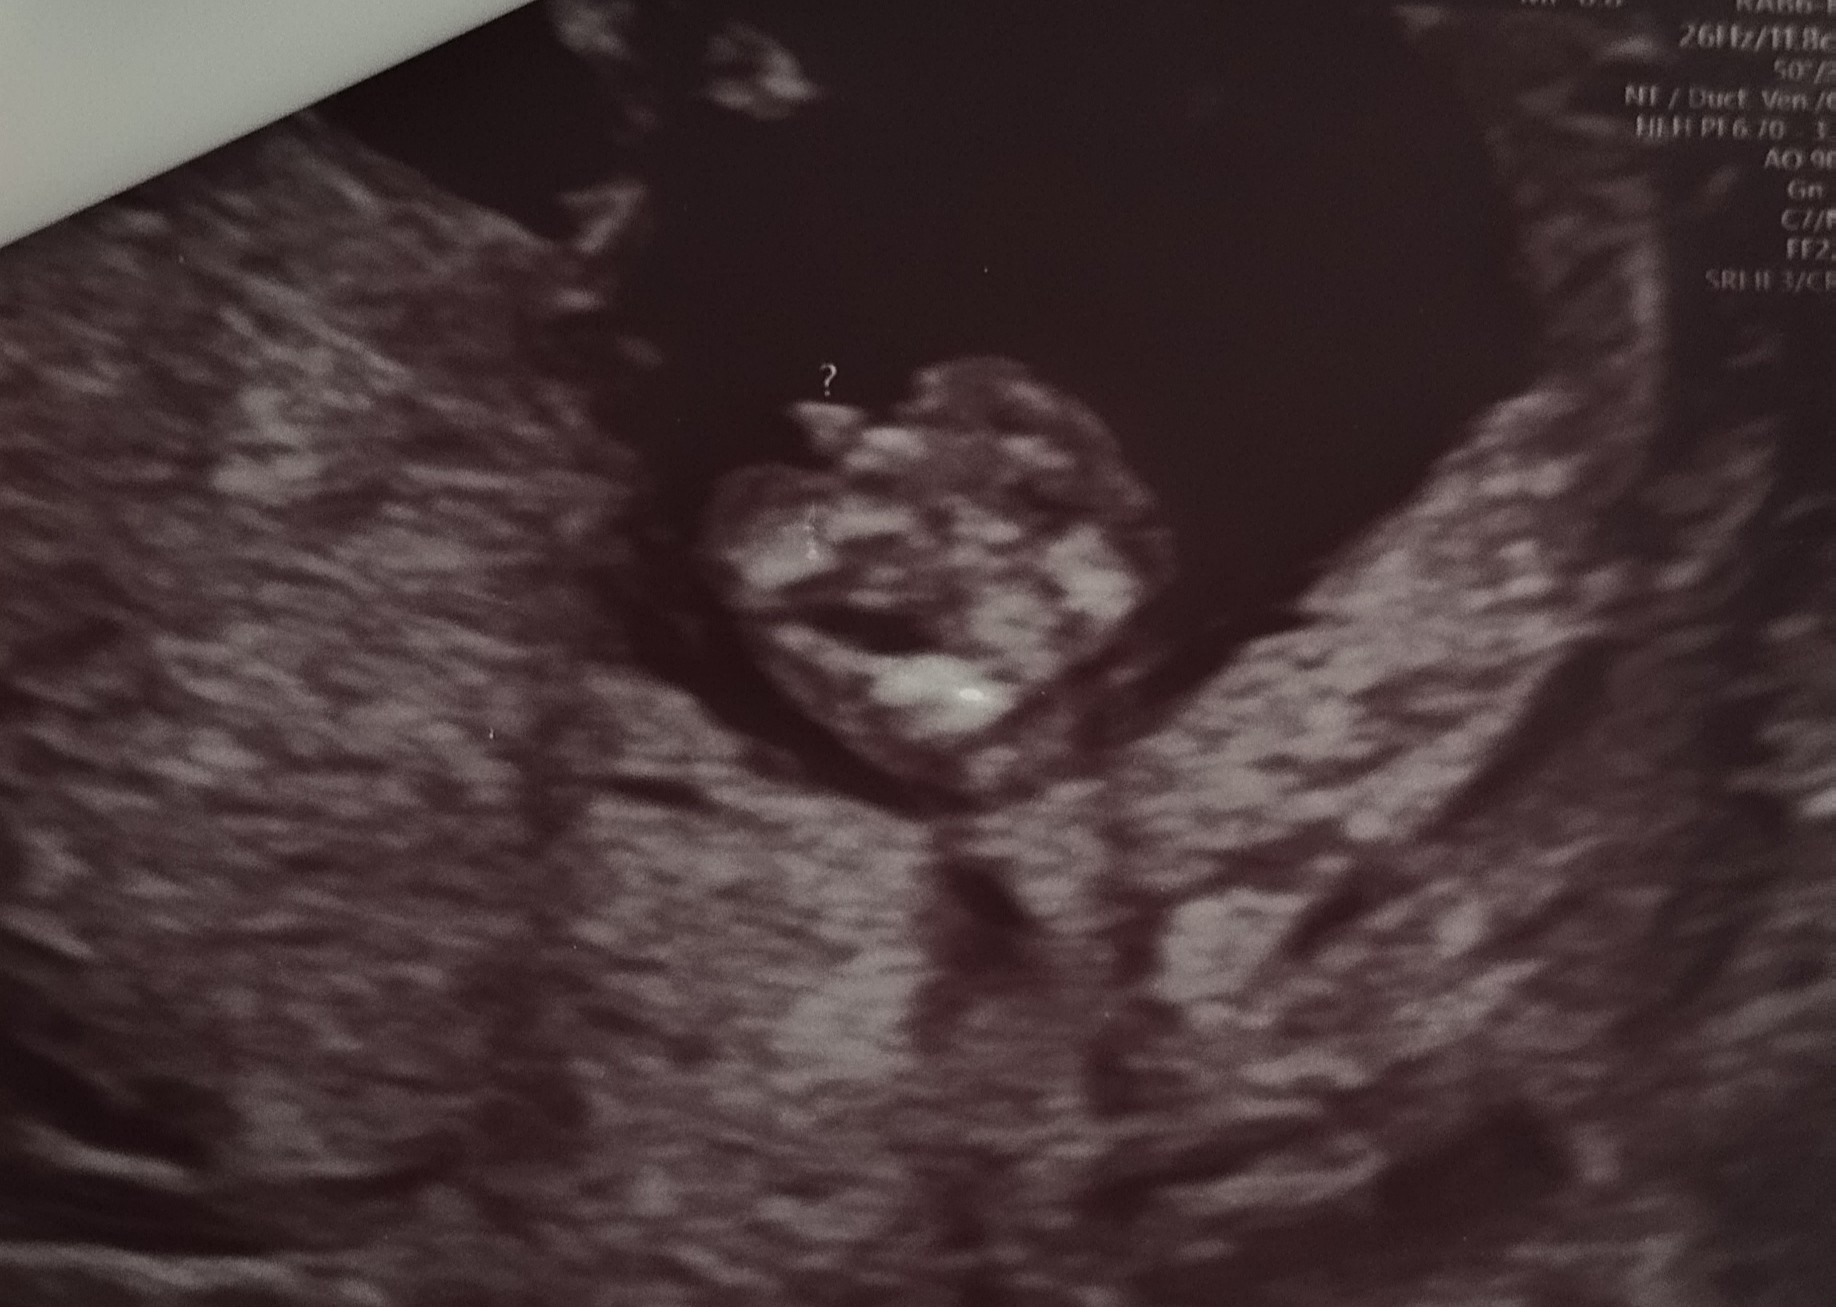

Cześć! Jak wy uważacie bardziej chłopak czy dziewczyna? Może wszystko się jeszcze zmienić ? Za wcześnie na określenie płci ?

Pan doktor dał znak zapytania, niby dla niego chłopak tak na 85% .